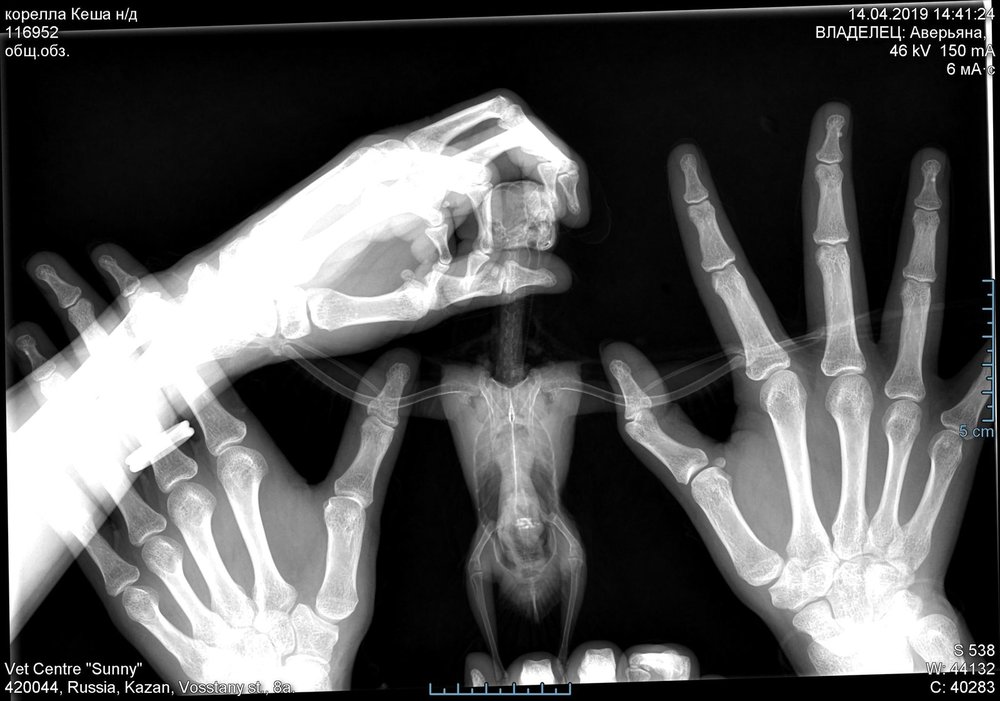

Ещё делали рентген.

корелла_Ке_нд_2019-04-14_14-41-24_общ_обз_.jpg

...В рентгене не силён. По мне, печень в норме, зоб не вздут... Что с воздухоносными мешками -- не могу сказать, нужно чтоб @Zosia посмотрела.